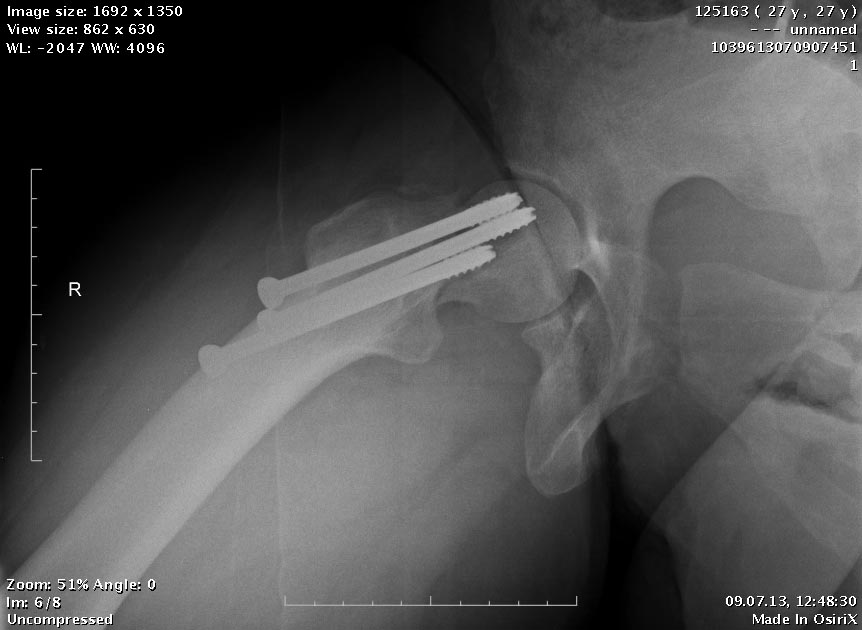

Две несросшихся шейки бедра, пацинтка 27 лет, травме 5 месяцев

БИОС плеча, Чкдо на л/запястный сустав, Биос левого бедра, Мос правой шейки бедра винтами.

Причина обращения -выявленный ложный сустав шейки левого бедра. При дообследовании выявлен несросшийся перелом шейки бедра на винтах.

Опороспособность обеих н/конечностей резко снижена, может стоять на правой, передвигается на каляске.Что думаем: слева однозначно протез, но бедро не срослось, менять гвоздь на пластину, пластина или которкая, или опасность конфликта с ножкой протеза, можно подождать консолидации и разбираться с правой конечностью.Справа остесинтез с коррегирующей остеотомией, но смущает состояние верхнего полюса после миграции винтов, что может повлечь протезирование на фоне нарушения анатомии проксимального бедра, что не хорошо для выживаемости протеза у 27 летней пациентки. Может сразу протез ?КТ головки не информативна из-за винтов

Alexander Chelnokov 13 Июль 2013, 00:23

Пациентка приехала на этой неделе. Сегодня сделали правое бедро. Удалили винты, сделали чрескожную вальгизирующую остеотомию, зафиксировали Affixus. Второе бедро будем делать недели через 2.

Добрый день! Коллеги! Складывается впечатление, что вальгизация выполнена на уровне перелома шейки бедренной кости, а не в межвертельной зоне, непонятна возможность компресси в зоне перелома (винты позиционированы резьбовой частью в зоне перелома). и уж совсем не понятно статическое блокирование дистальной части штифта. С уважением Ушаков С.

Головка до и во время остеотомии была диафиксирована несколькими спицами, так что положение ее не менялось. На картинке подрисован диафиз, был он примерно там. Дистальный винт введен больше на всякий случай, чтобы дистальный конец гвоздя не болтался. А большой винт проходит через периферический отломок, так что введение динамического винта внизу ничего не дало бы.